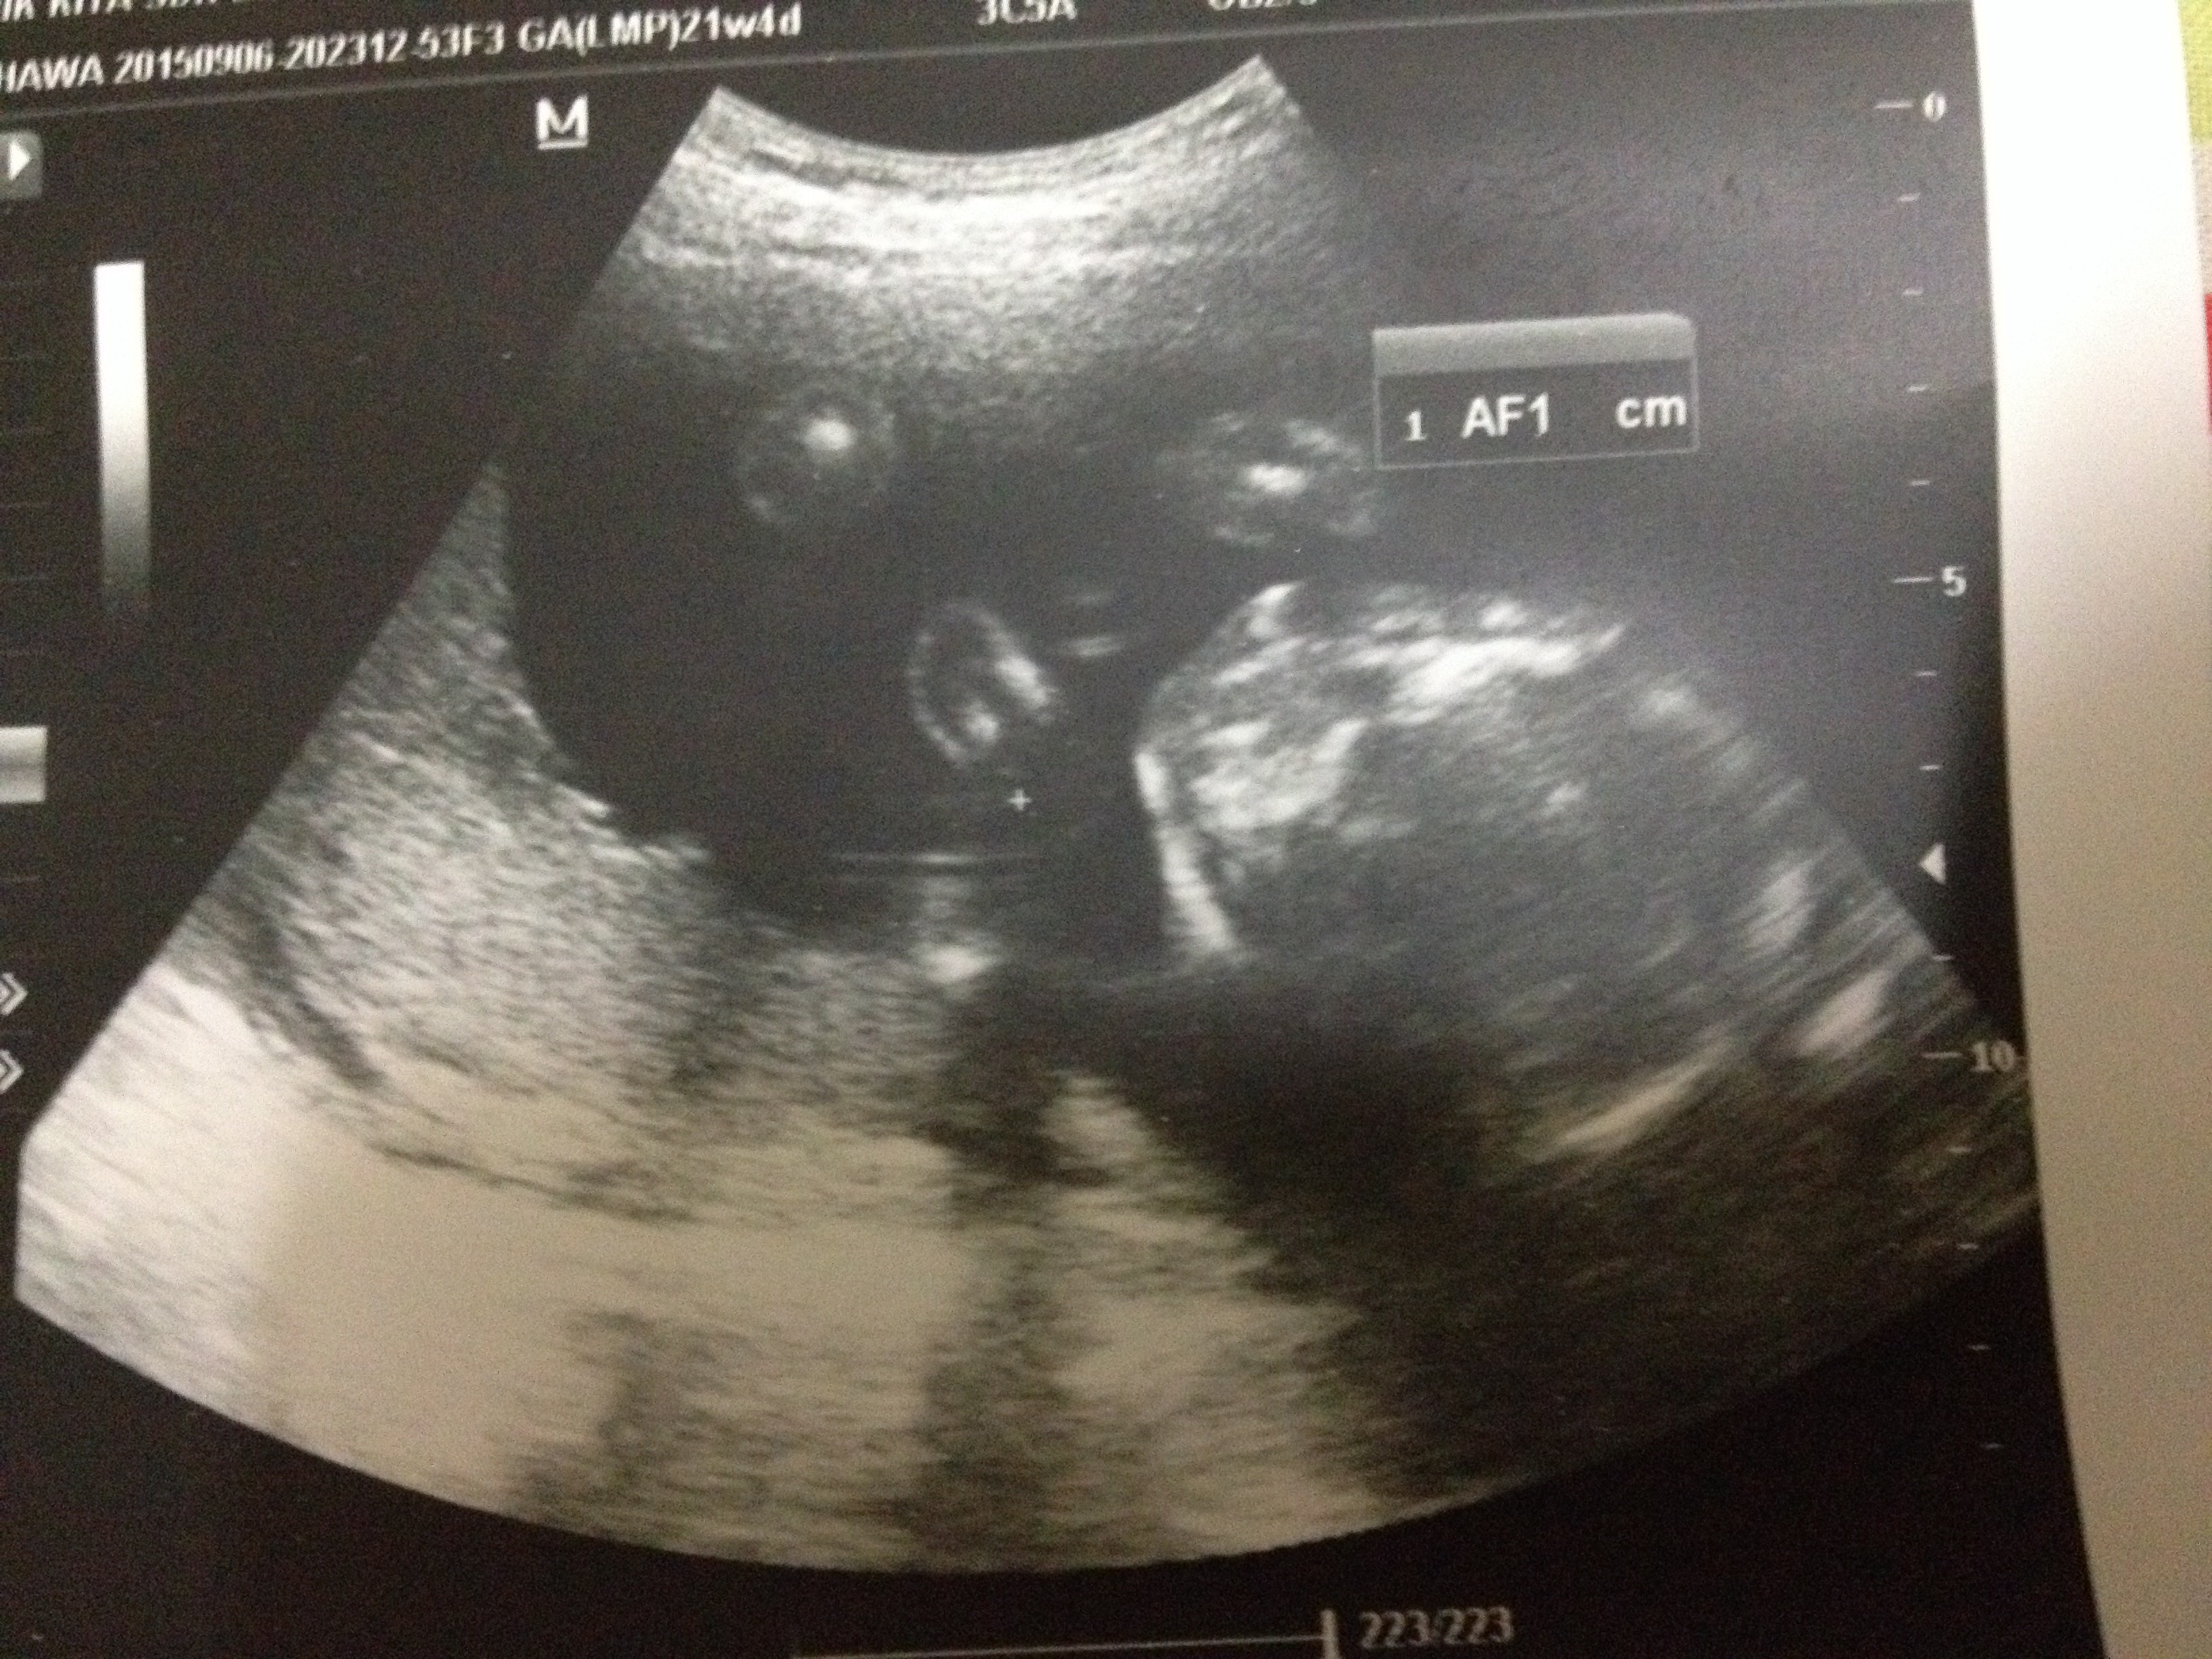

21 wk u/s gender scan

just wondering if this scan is of the genital area? Dr took a few shots and prints this one and I'm clueless if its a bottom shot of the genital area.

Dr says it looks like I'm having a girl...

Thanks jenjackson14 and u are right. I asked dr to do scan and see baby gender if possible and if everything is ok and she said looks like your having a girl and after appointment reception hands me this particular u/s pic and i was thinking which body part is this. Is it the head or bottom shot of genital area.

• I thought it looked like the head personally..lol...but congratulations on ur baby girl!!! If I were a stranger on the street I would still love to see it, and make a guess.. ;)